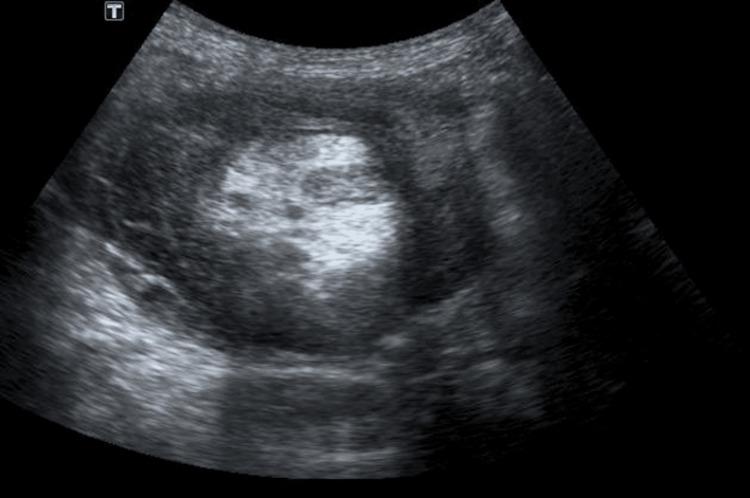

We report a rare case of a 32-year-old male diagnosed with a mass of intussusception in the right lumbar region. Adult intussusception has a prevalence of less than 5%. Among all cases of intestinal obstructions, adult intussusception is found to be only 1-3%. Adult intussusception of the bowel is uncommon. In contrast to intussusception in children, the traditional trio of palpable sausage, jelly stools, and discomfort is rarely seen. Adults usually present with nonspecific findings that last for a long time. We share the case of a patient who presented with complaints of pain in the abdomen and loss of appetite for six months. In addition, the patient also complained of constipation. The patient had a history of easy fatigue on moderate-intensity activity. Ultrasonography of the abdomen was suggested which revealed bowel wall thickening in the subhepatic region, with likely intussusception and formation of a lump with few enlarged lymph nodes adjacent to it. A confirmatory diagnosis was made after a computed tomography scan. In all cases, surgical intervention is required, and an organic lesion inside the invaginated section of the colon is discovered to be the lead point in up to 90% of cases. The laparoscopic procedure can be used for both diagnostic and therapeutic purposes. A right hemicolectomy was performed through a vertical midline incision. The patient was referred to the physiotherapy department for further management.

我们报告了一例罕见病例,一名32岁男性被诊断为右腰区套叠性肿物。成人肠套叠的患病率低于5%。在所有肠梗阻病例中,成人肠套叠仅占1% - 3%。成人肠套叠并不常见。与儿童肠套叠不同,传统的可触及腊肠样包块、果酱样大便和不适三联征很少见。成人通常表现为持续时间较长的非特异性症状。我们分享一名患者的病例,该患者主诉腹痛和食欲不振六个月。此外,患者还抱怨便秘。患者有在中等强度活动时容易疲劳的病史。建议进行腹部超声检查,结果显示肝下区域肠壁增厚,可能存在肠套叠并形成肿块,其附近有少数肿大淋巴结。计算机断层扫描后做出了确诊。在所有病例中,均需要手术干预,在高达90%的病例中,发现结肠套叠段内的器质性病变是套叠的起始点。腹腔镜手术可用于诊断和治疗目的。通过垂直正中切口进行了右半结肠切除术。患者被转诊至理疗科进行进一步治疗。